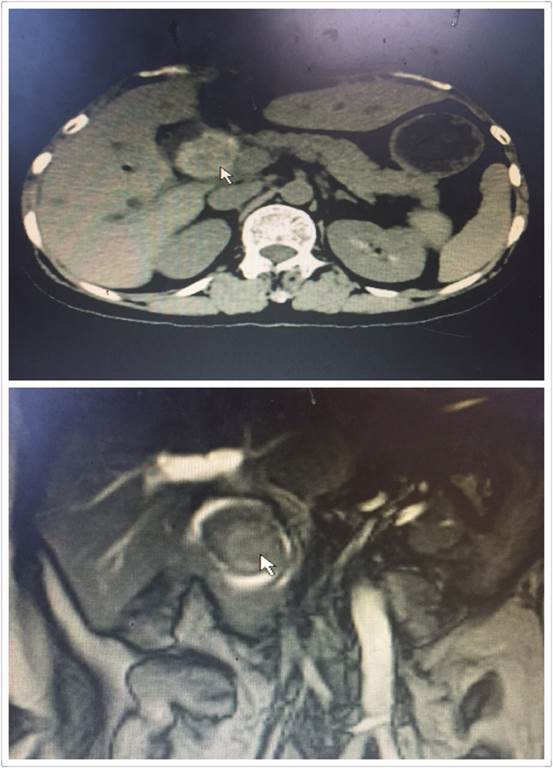

腹腔鏡手術(shù)雖好,但是對于有腹部多次手術(shù)史、腹腔廣泛粘連的患者來說,由于腹腔解剖結(jié)構(gòu)改變,腹腔鏡手術(shù)倒變成了雷區(qū)。近日,肝膽外科收住了一位老年患者,進(jìn)院時已出現(xiàn)了腹痛、發(fā)熱、黃疸。進(jìn)一步檢查后顯示,患者膽總管結(jié)石阻塞膽管,膽道擴(kuò)張,肝功能差,急需手術(shù)治療(見圖1)。然而這位患者似乎有些“命途多舛”,在這之前她就曾因膽管結(jié)石、腸梗阻在外院作了三次大手術(shù),所以腹部留下了整整長約30CM的手術(shù)疤痕(見圖2)。外院的醫(yī)生了解到該情況后建議直接“開刀”,患者通過打聽得知我院腹腔鏡技術(shù)精湛,遂慕名而來。

圖1